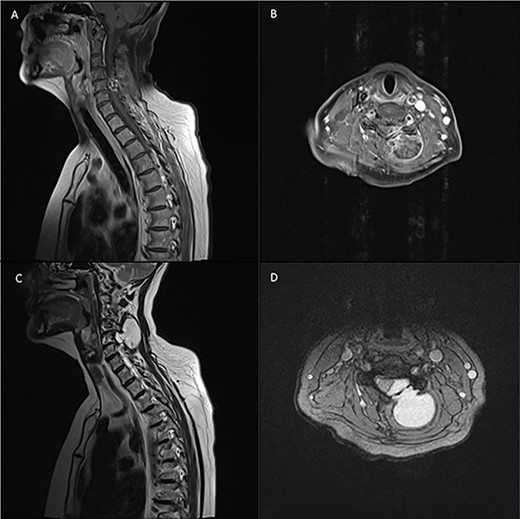

Pre-operative spinal imaging showed a well-circumscribed, cystic parasagittal spinal mass eroding through the lamina and pushing the thecal sac and largely indicative of a paraspinal myxoma (Fig. 1). The patient underwent a biopsy in the first instance to guide diagnosis and subsequently proceeded to resection of the tumour.

Pre-operative T1 and T2 weighted MRI: left-sided extra-axial mass at C4/5 hypointense on T1 and hyperintense on T2.